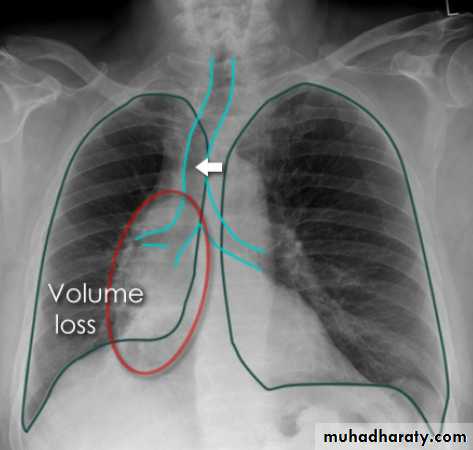

Left lower lobe collapse has distinctive features, and can be readily identified on frontal chest radiographs, provided attention is paid to the normal cardiomediastinal contours. The shadow cast by the heart does however make it harder to see than the right lower lobe collapse

Radiographic features

Left lower lobe collapseis readily identified in a well penetrated film of a patient with normal sized heart, but can be challenging in the typical patient with collapse, namely unwell patients, with portable (AP) often under-penetrated films, often with concomitant cardiomegaly. Features to be observed include :

triangular opacity in the posteromedial aspect of the left lung

edge of collapsed lung may create a 'double cardiac contour'

left hilum will be depressed

loss of the normal left hemidaphgragmatic outline

loss of the outline of the descending aorta

Non-specific signs indicating left sided atelectasis are usually also be present including:

elevation of the hemidiaphragm

crowding of the left sided ribs

shift of the mediastinum to the left

On lateral projection the left hemidiaphragmatic outline is lost posteriorly and the lower thoracic vertebrae appear denser than normal (they are usually more radiolucent than the upper vertebrae) .